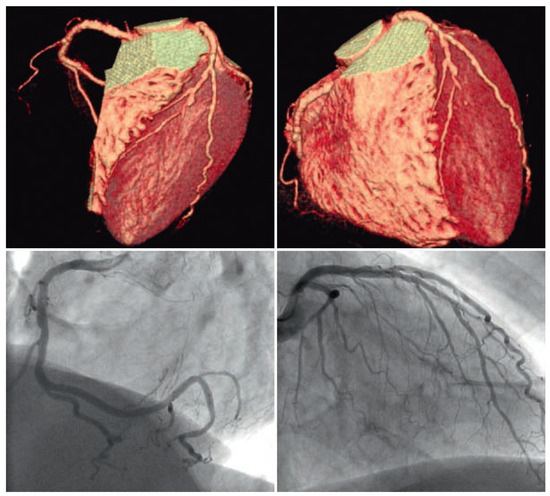

Coronary CT angiography (CTA) is emerging as a highly effective alternative imaging technique for the assessment of coronary artery disease (CAD). The rapid evolution of multidetector CT scanners has lead to major improvement in temporal resolution o...